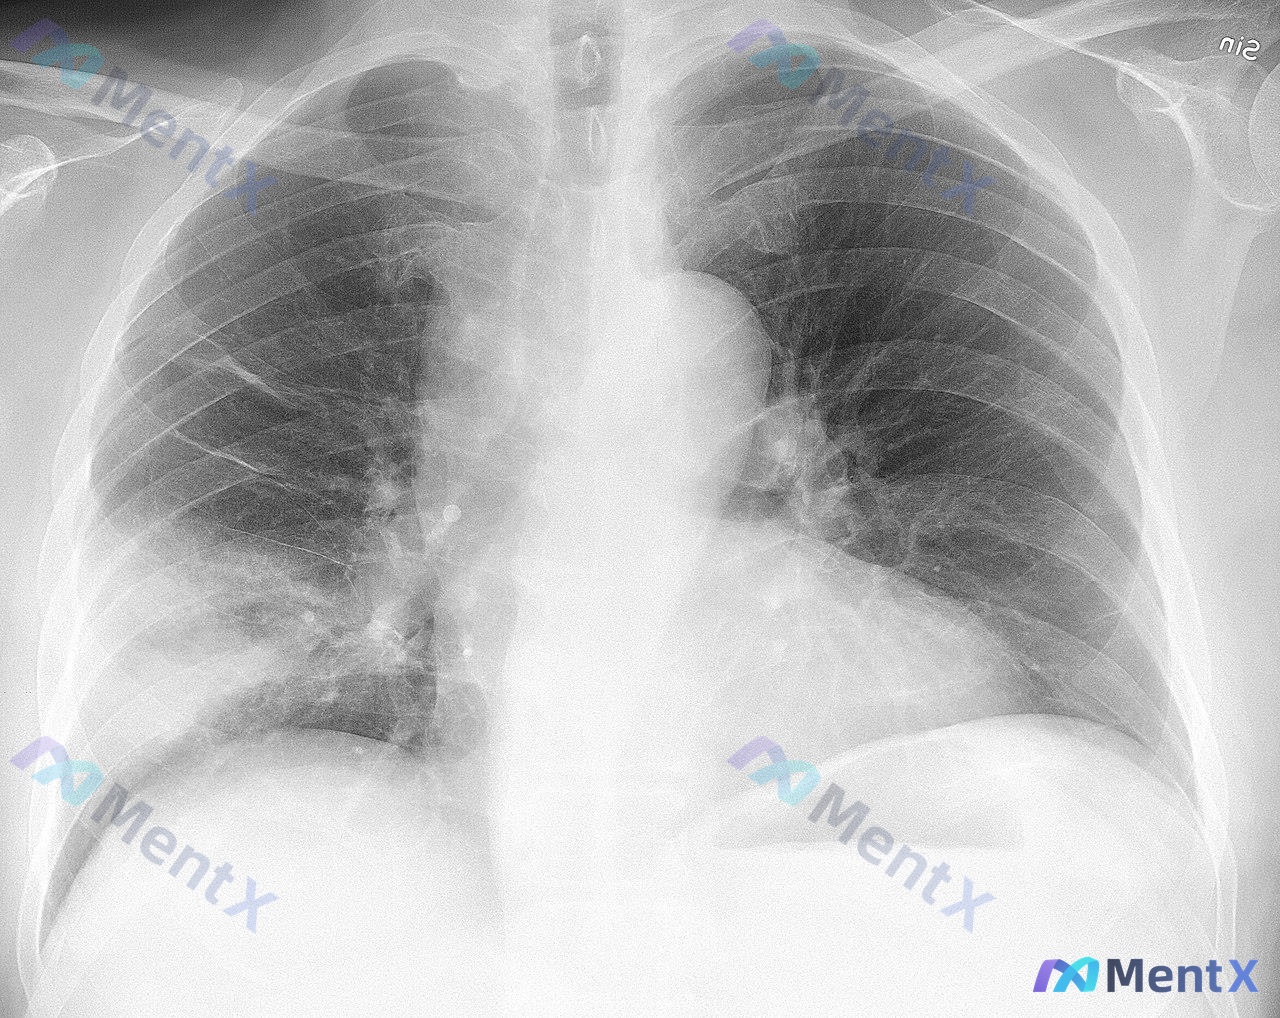

影像:胸片显示右肺中下野大片状密度增高影,边缘模糊,可见支气管充气征。左肺及胸膜腔未见明显异常。